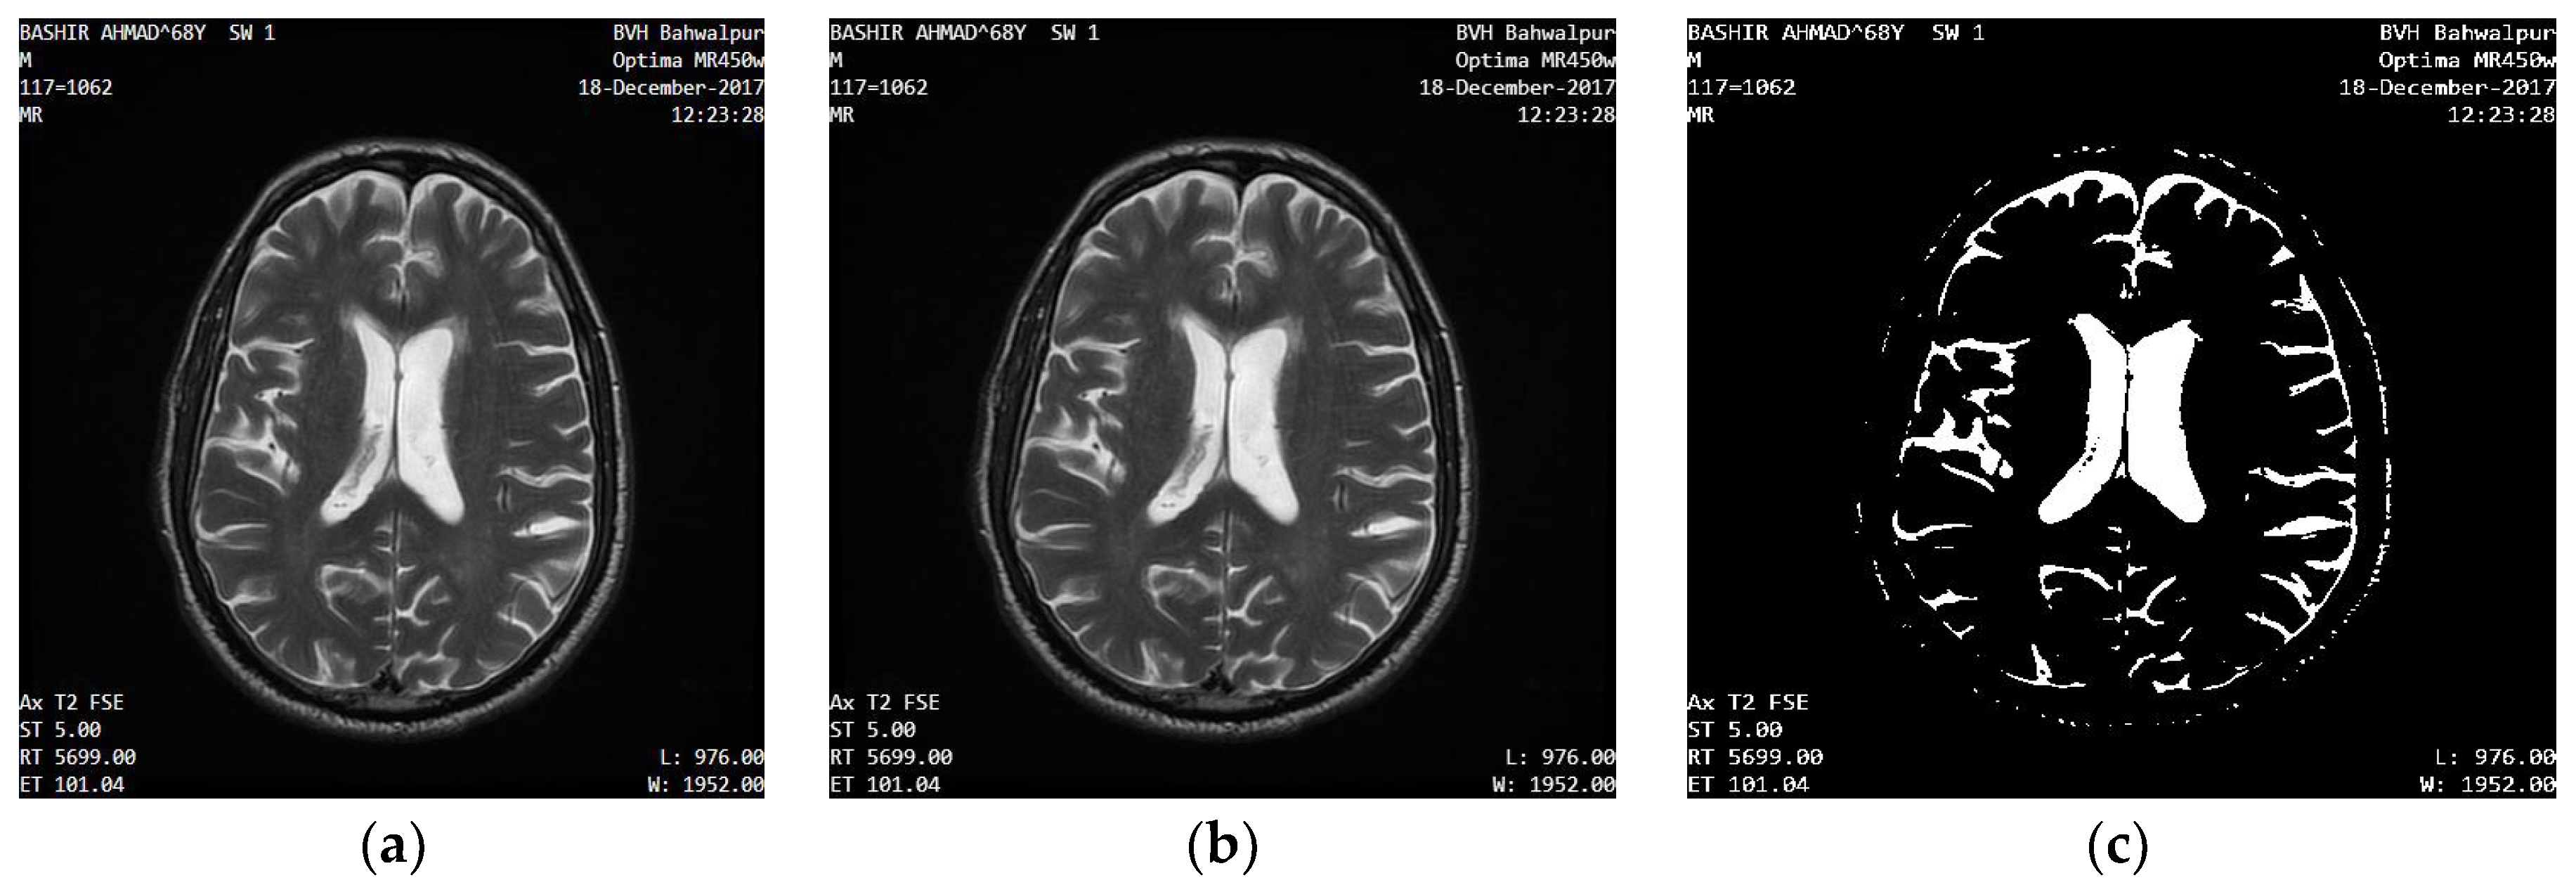

2.2.1. Input Human Brain MR Images

2.2.2. Bitmap Conversion

2.2.3. Noise Removal

2.2.4. Grayscale Conversion

2.2.5. Image Enhancement

2.2.6. Image Binarization

2.2.7. Area Segmentation using Watershed Algorithm